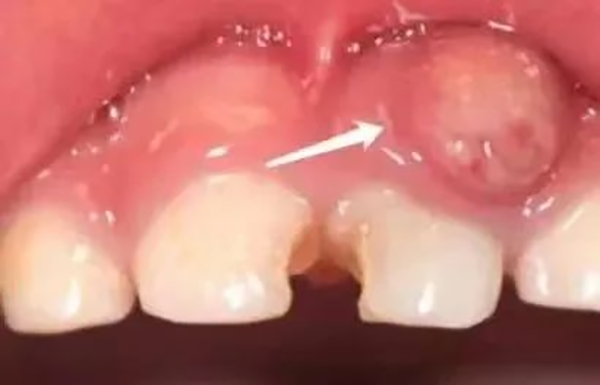

三、根尖炎引起的疼痛

孩子不仅牙疼,而且牙龈或面部出现肿胀,甚至还伴随着发烧等全身症状。这意味着牙齿的病变已经进展到根尖周围组织了。这种情况较为严重,需要立即到口腔科治疗牙齿,并进行抗炎治疗。

牙根尖炎